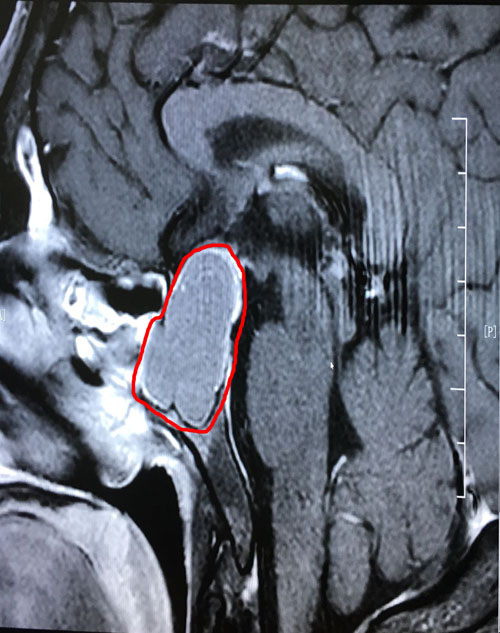

术前影像显示:垂体巨大腺瘤,突破鞍隔向上生长

到院后,李士其教授和潘仁龙主任一起,研究讨论了患者病情:由于患者颅内鞍区的肿瘤很大(约1.8*3.1公分),已严重影响到患者的垂体功能,并压迫视神经,感觉神经等功能。李士其教授表示:手术是刻不容缓的事,待患者检查结果出来,没有手术禁忌,就可以立即实施手术。

一切准备就绪后,2月23日下午,李先生被送进了手术室。麻醉顺利后,李士其教授采用“经鼻蝶窦入路垂体瘤切除术”微创手术方式。在双荧光显微镜下,李教授从患者右侧鼻腔入路,分块切除肉色肿瘤物,然后剥离取出。